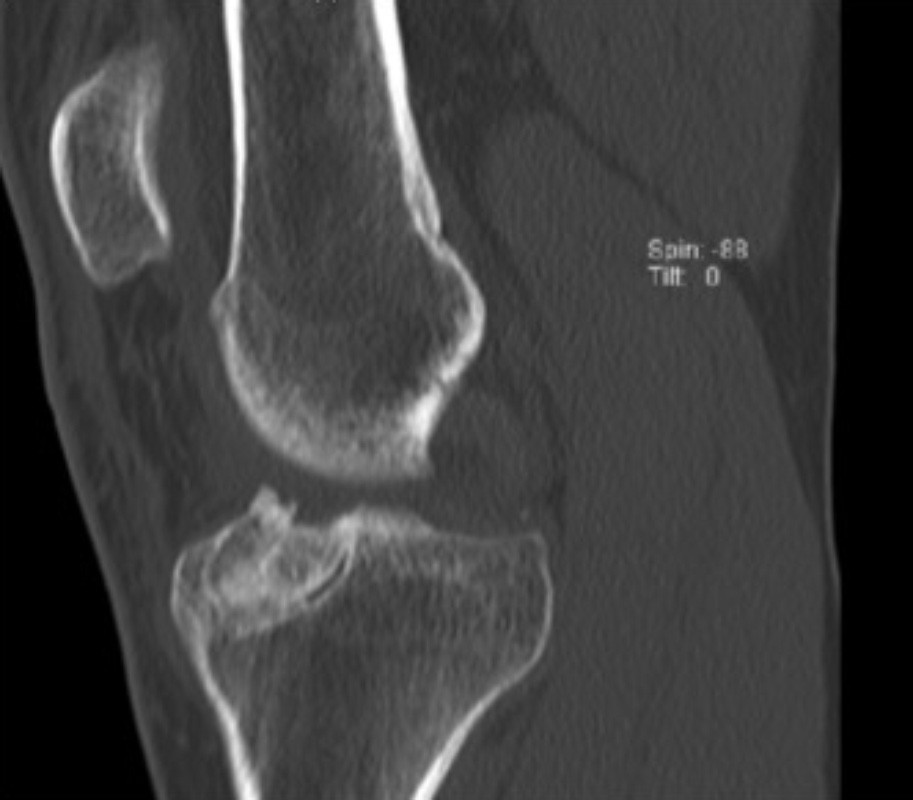

Die Einheilung des Knochens wird 3 Monate nach der Implantation mittels eines CTs überprüft. Anschließend kann in einem zweiten Eingriff eine erneute Kreuzbandrekonstruktion durchgeführt werden.

Versorgung knöcherner Ausrisse des vorderen und hinteren Kreuzbandes

In seltenen Fällen kommt es zu knöchernen Ausrissen des vorderen Kreuzbandes. Diese Form der Verletzung ist bei Kindern häufiger als bei Erwachsenen. Hierbei bleibt das Kreuzband intakt während es mit einem knöchernen Bruchstück aus dem Schienbeinkopf ausreißt. In diesen Fällen kann das ausgerissene Knochenstück und somit auch das Kreuzband mittels einer Schraube oder durch stabile Nähte die durch Bohrkanäle ausgeleitet werden refixiert werden. Somit ist eine vollständige Ausheilung dieser schweren Verletzung möglich.